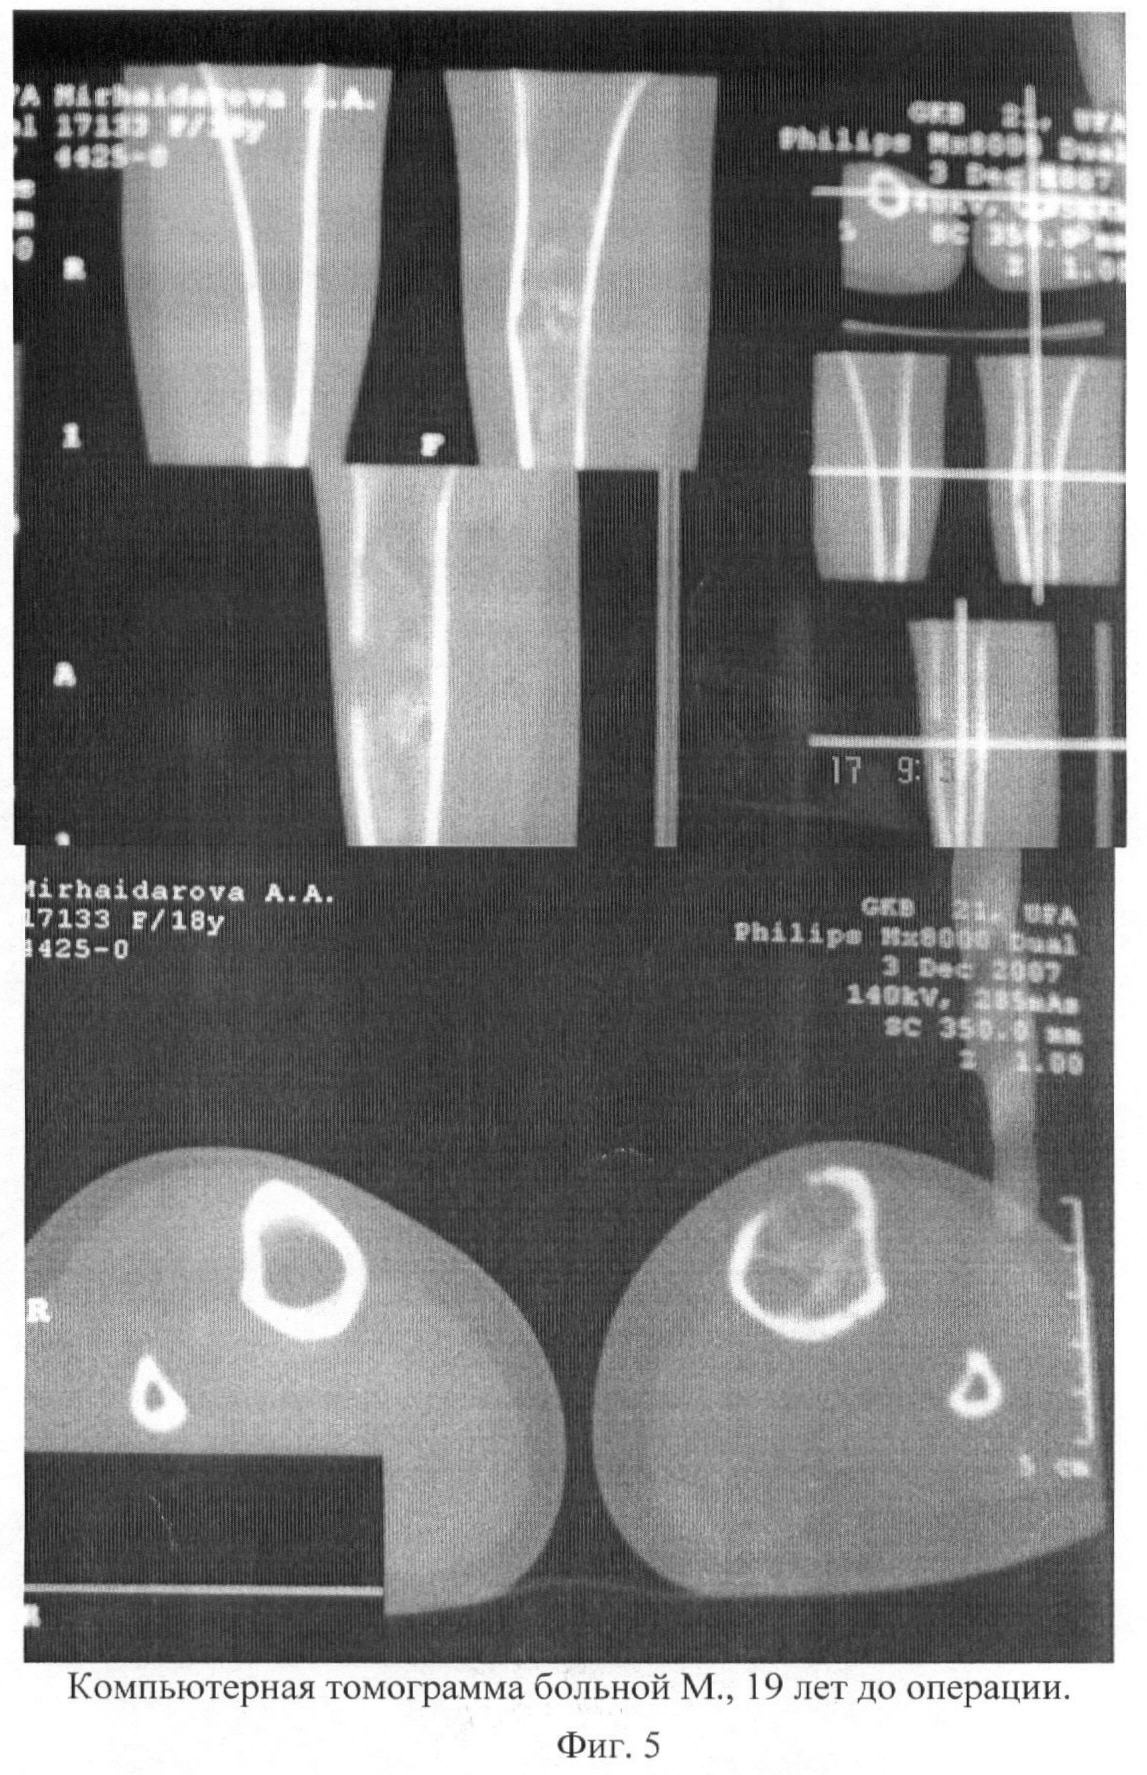

Больной проведено обследование: компьютерная томография обеих голеней, рентгенография, операционная биопсия костной ткани и полости кисты (цитологическое, гистологическое и бактериологическое исследование костной ткани). Данные гистологического, цитологического исследования: атипичные клетки не выявлены. Роста микрофлоры при бактериологическом посеве не обнаружено. Имеется опасность патологического перелома в зоне очага аневризмальной кисты, так как толщина кортикального слоя костной ткани составляет 1-2 мм. (фиг.5-7).